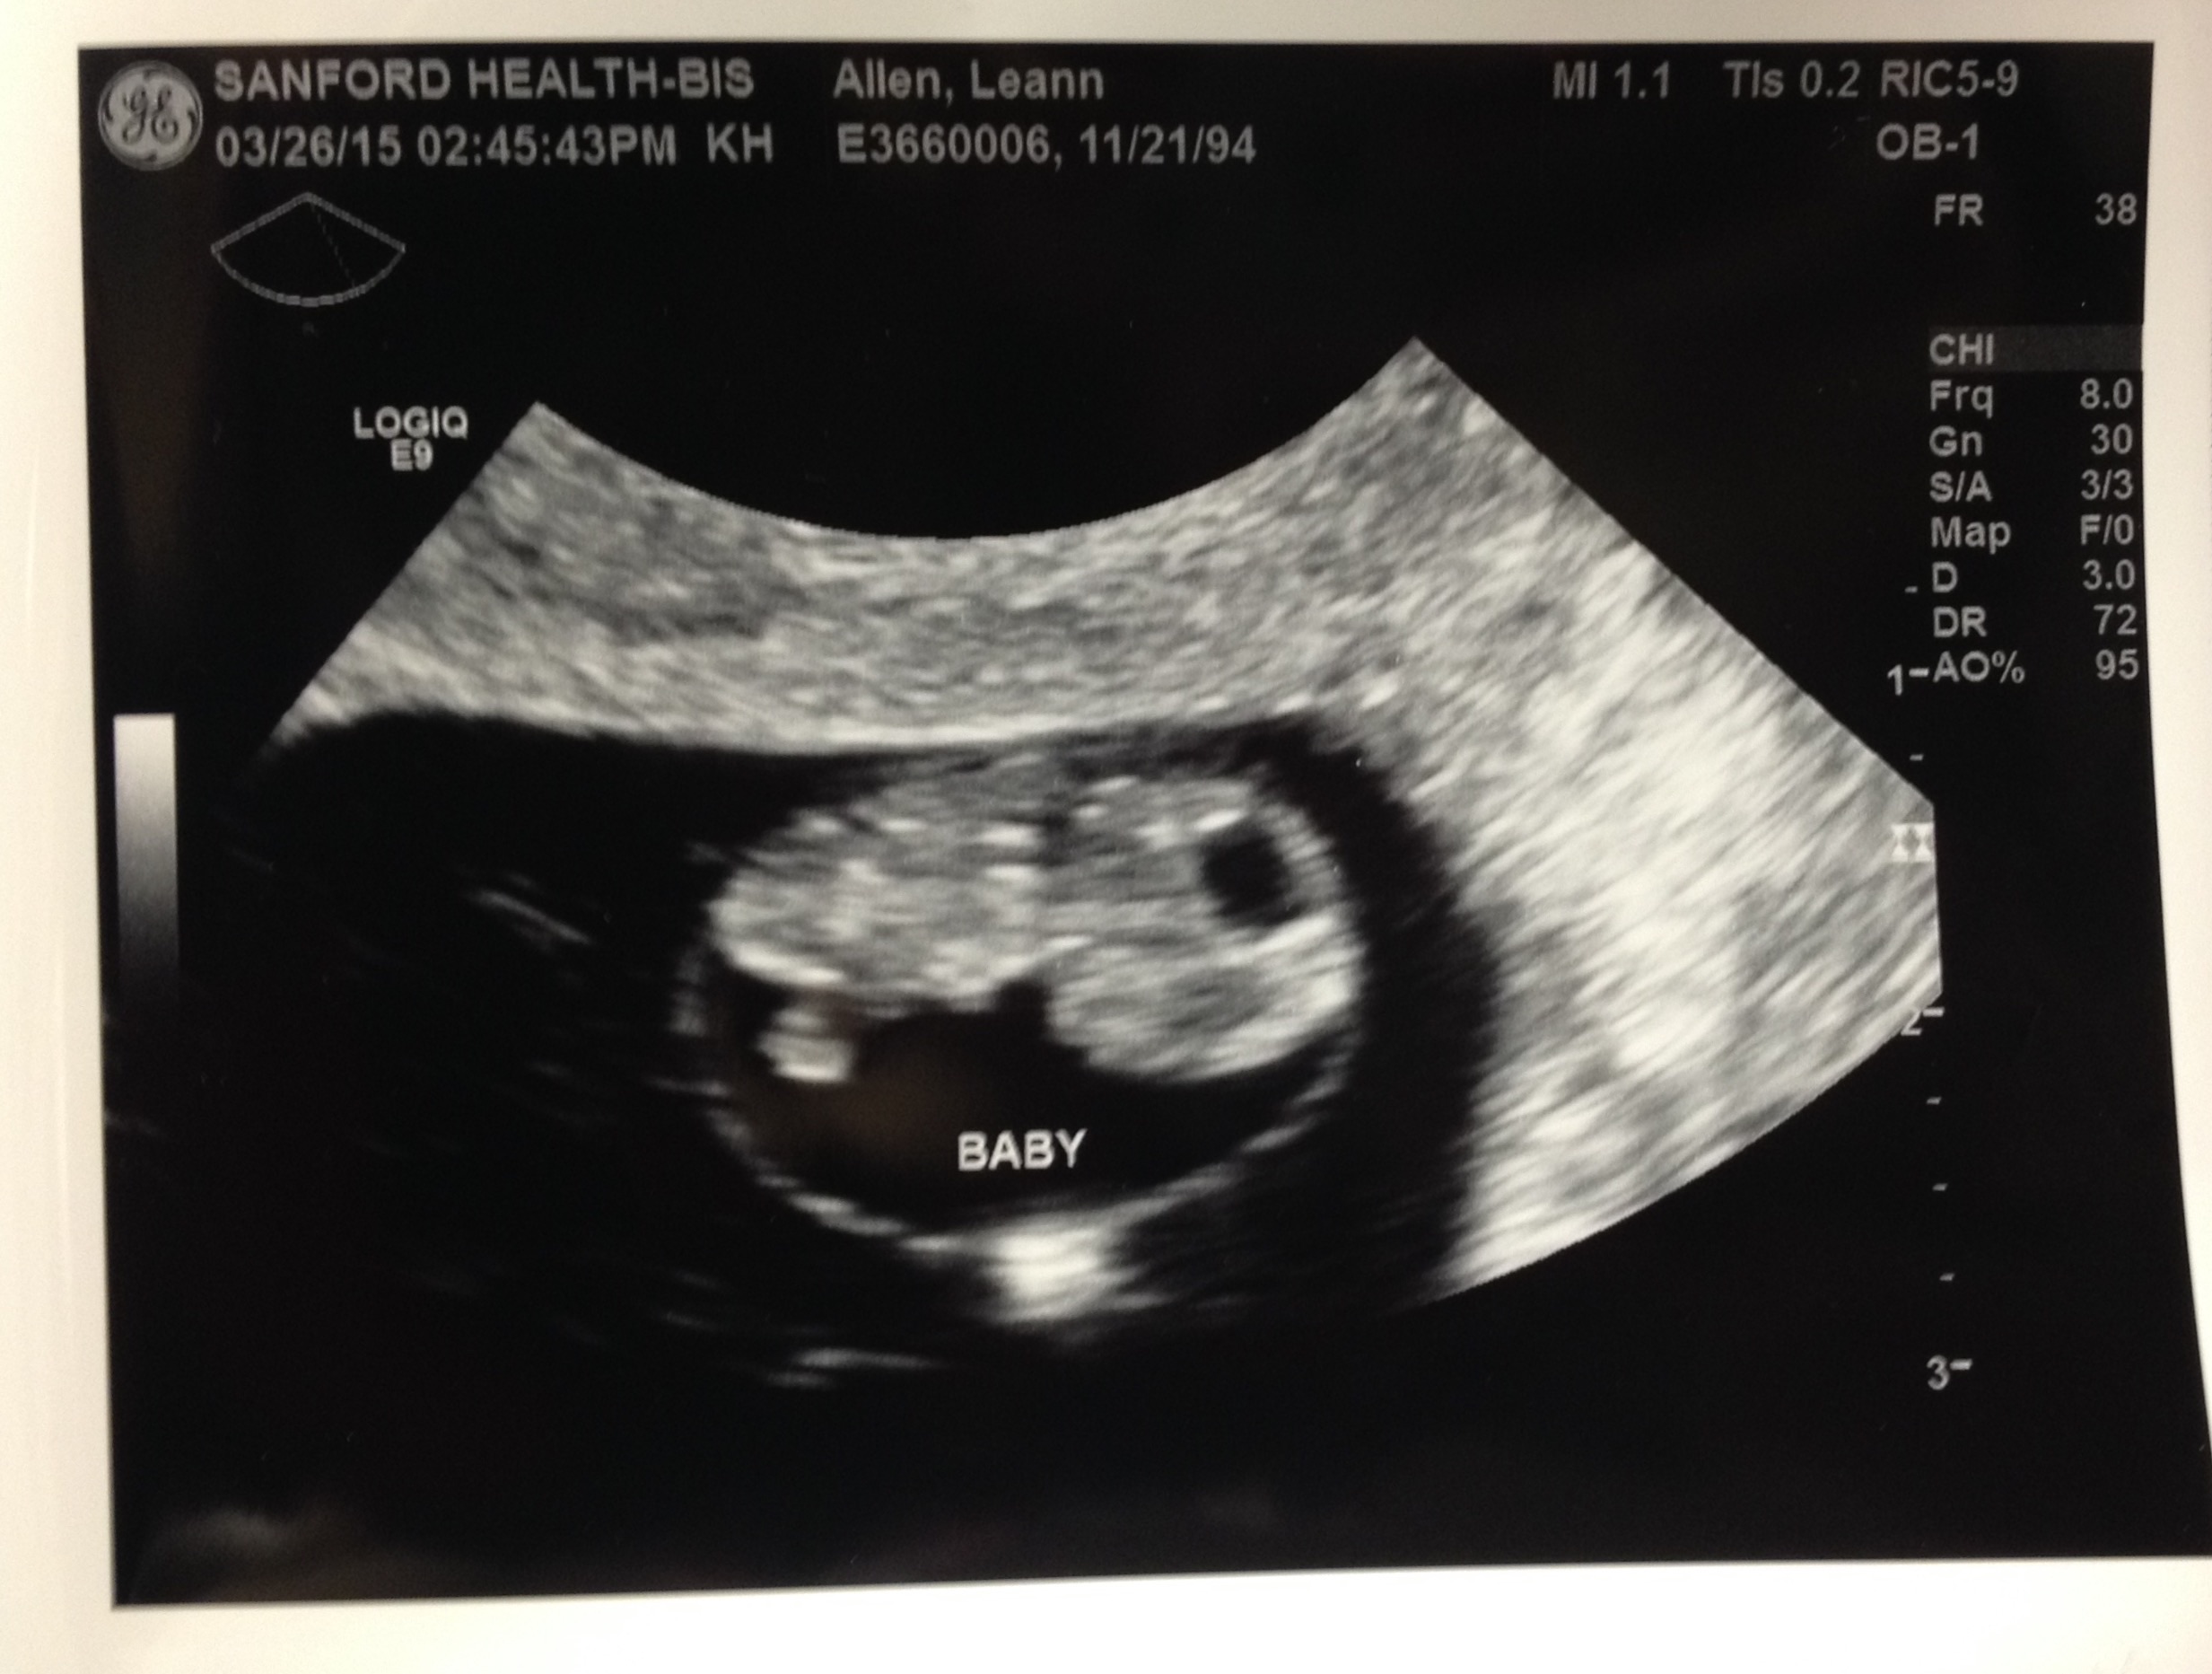

Our 10 week scan that we had this last Tuesday 4/7. Baby measured 10w5d with a heartbeat of 160 bpm. It was a great day for husband and I, not to mention how adorable those little wiggle wiggles were. omgosh, just melted my heart. I am so in love